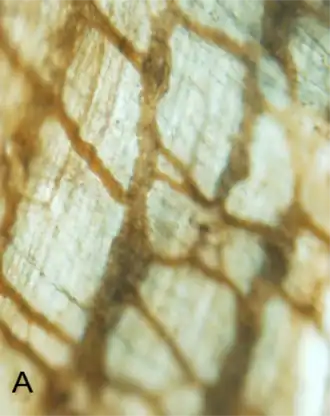

Lichtmicroscopische eigenschappen

Onder de lichtmicroscoop vertoont de interstitiële cel van Cajal (ICC) een spoelvormige of driehoekige structuur met dunne polaire cytoplasmatische uitlopers. Het ICC heeft zowel een goed ontwikkeld glad als ruw endoplasmatisch reticulum.

Het vertoont gap junctions die het verbinden met gladde spiercellen en andere aangrenzende ICC's.[10]